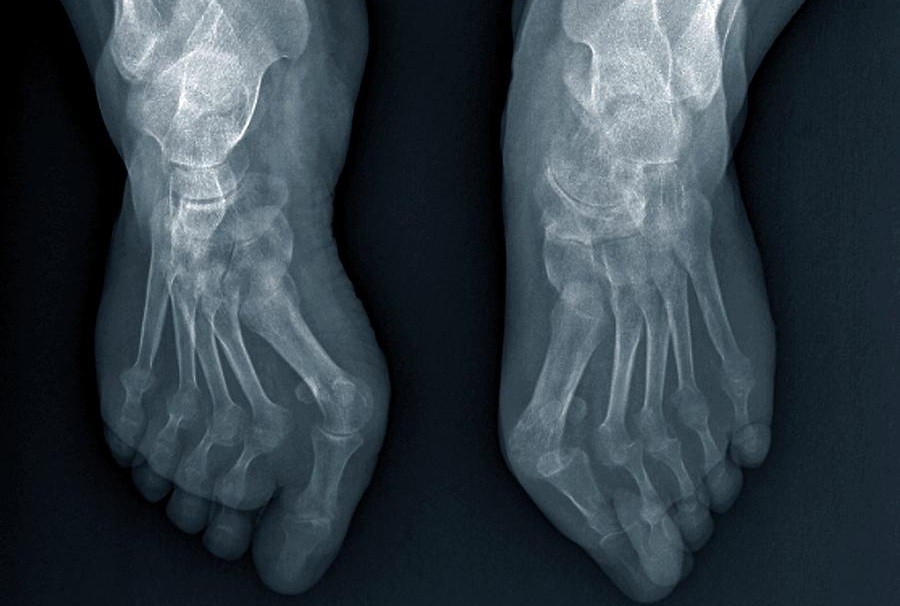

— Apakah Anda benar-benar berpikir bahwa pijat atau analgesik dapat mencegah kerusakan sendi dan tulang rawan? Itu adalah kesalahpahaman besar. Obat-obatan dari apotek tidak dapat meregenerasi jaringan, sementara bahan kimia yang terkandung di dalamnya justru merusak hati dan ginjal seiring waktu. Tubuh tidak dapat selamanya menanggung beban racun ini, dan alih-alih menyelesaikan masalah, Anda justru meracuni diri sendiri! Hal ini terutama berlaku untuk tulang belakang. Semua sendi mengalami keausan, tetapi pada tulang belakang, kurangnya ujung saraf dapat menyembunyikan perubahan yang berbahaya. Kompresi saraf skiatik akibat hernia adalah proses yang menyakitkan, awalnya menyebabkan nyeri ringan di punggung bawah, lalu menjalar ke kaki, menyebabkan kesemutan, mati rasa, dan akhirnya hilangnya fungsi kaki sepenuhnya. Kerusakan yang terus berkembang akan menyebabkan kelumpuhan pada bagian bawah tubuh, dan mengembalikan kendali atasnya menjadi hampir tidak mungkin. Lihat gambar ini. Ini adalah kondisi tulang belakang seseorang yang baru berusia 44 tahun, tetapi tampak seperti lansia. Dulu, kerusakan seperti ini hanya terjadi setelah usia 60 tahun, tetapi sekarang hal ini menjadi umum bagi mereka yang baru saja melewati usia 40 tahun. Kerusakan ini akan terus berkembang seiring bertambahnya usia, dan mengabaikannya berarti menempatkan diri dalam risiko kelumpuhan total!

Tulang belakang pasien berusia 44 tahun: semuanya dimulai dengan nyeri ringan, tetapi hanya dalam satu minggu muncul hernia, dan dalam dua minggu terjadi pergeseran tulang belakang, tekanan pada saraf, dan akhirnya—kursi roda.